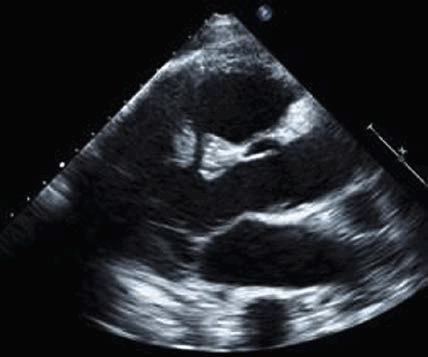

Чтобы оценить молотящий митральный клапан:- Получите стандартный вид парастернальной продольной оси, показывающий митральный клапан. Оцените нормально ли встречаются кончики створок митрального клапана (т. е. касаются друг друга чуть ниже фиброзного кольца)? Или кончик одной створки пролабирует или свободно движется и возвращается в левое предсердие в систолу?

- Поместите цветной допплеровский сектор на митральный клапан и левое предсердие. Посмотрите есть ли струя митральной регургитации (высокоскоростной или турбулентный пятнистый поток в систоле)? Во многих случаях он будет направлен эксцентрически либо к передней, либо к задней стенке левого предсердия. Как правило, молотящая створка МК направляет струю MР в сторону от самой поврежденной створки.

- Повторите двумерное (2D) изображение и цветное допплеровское сканирование митрального клапана в апикальном четырехкамерном и апикальном трехкамерном срезе. По техническим причинам низкое качество изображения нередко препятствует абсолютному определению того, есть ли молотящая створка МК, но есть эксцентрическая струя значимой МР или хордальная структура, колеблющаяся в левом предсердии проксимальнее митрального клапана, что повышает вероятность разрыва митрального аппарата.